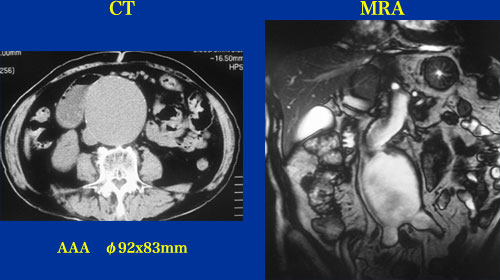

68歳 男性

【起始・経過】

2007年3月ごろ拍動性腫瘤を自覚。

2007年4月AMIを発症し、他院でPCI(#11)施行。そのときφ8.5cmAAAを指摘され当院紹介となった。左腎動脈狭窄(Renovascular HTN)の疑いもある。

【既往歴】

高血圧(+) 糖尿病(+)  Recent AMI(PCI)

【治療計画】

Percutaneous Stentgraft (Gore Excluder)

左腎動脈ステント術

症例9,10 CTA